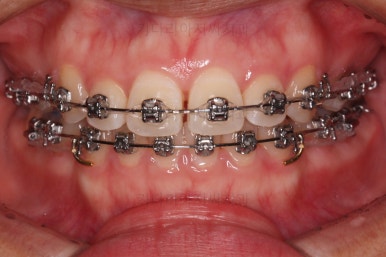

치열이 매우 바르게 되었고 교합도 양호하며 뻗쳐 있던 앞니 각도도 좋아졌네요.

돌출의 느낌도 처음보다 많이 좋아졌어요.

웃을 때 보이는 치열의 느낌도 좋고요.

전후 사진을 비교해 볼게요.

입술의 두께로 인한 돌출감 개선에 약간은 한계가 있었지만 그래도 본인이 만족한 수준에서는 돌출감을 개선했고 치열도 매우 가지런하게 마무리를 할 수 있었답니다.